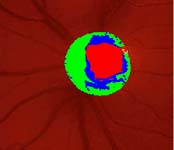

Očekávali byste protažení exkavace k hornímu pólu terče, jak nám ukazuje tento snímek z tomografu HRT II.

exkavace levé oko

Na kterém oku je exkavace větší, na pravém nebo na levém? Podle pohledu na fotografie jistě na levém.

exkavace pravé oko